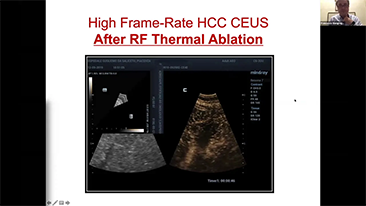

????? ??? ??? ??? ?? ?? ???? ????, ?????? ??? ?? ???? ?? ??? ??? ??? ??? ?? ???? ?? ???? ????? ???.

??? ?? ??? ?? ???? ? ??? ?? ??? ?? ??? ??? ??? ???. ???? ??? UWN+ ?? ?? ??? ?? MI??? ??? ??? ?? ?? ??? ?? ?? ?? ???, ?? ?? ?? ???? ??? ? ????.